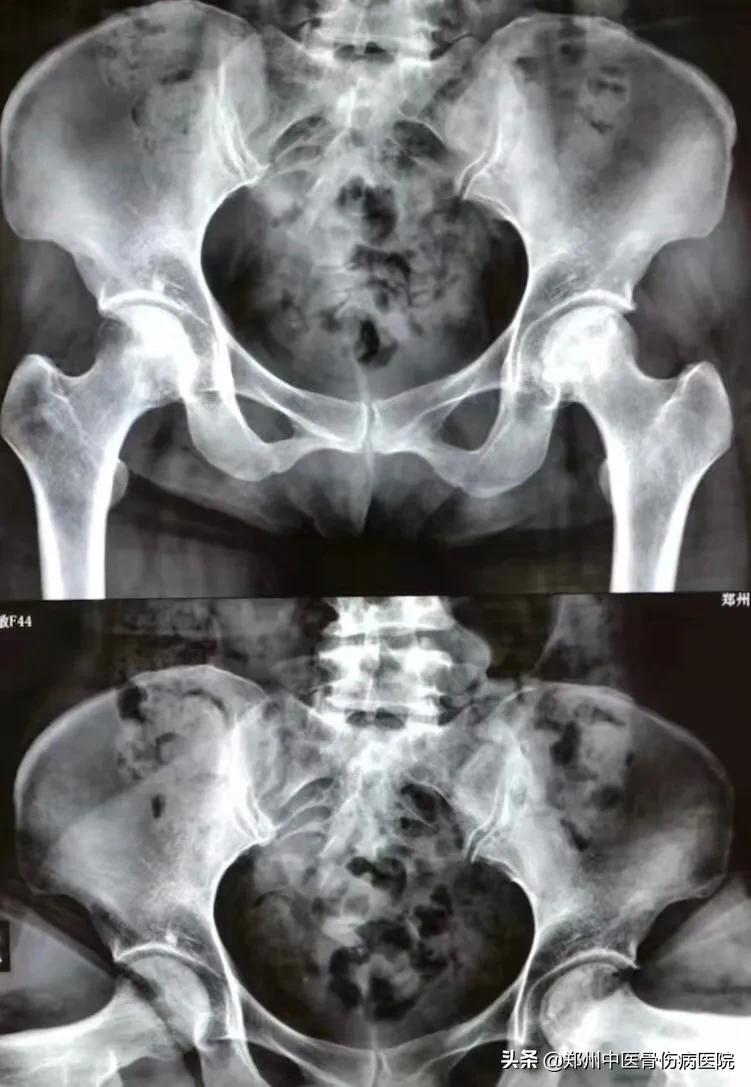

下图为患者康复前后照片对比:头型未再进一步塌陷,骨质密度也越来越均匀

① 患者康复前片子

② 患者康复后片子